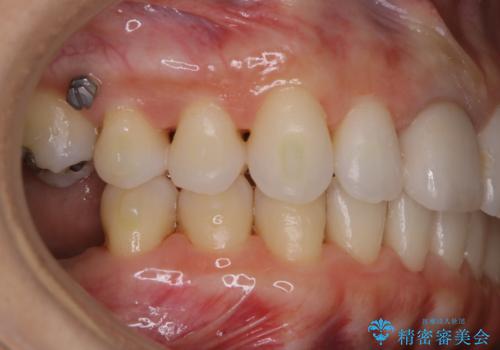

- インビザラインでのマウスピース矯正中にステインや着色を取りたいとのことでした。

PMTC60分コースを行いました。

PMTC(保険外治療)は、毎日の歯磨きで落としきれない汚れや、コーヒ、紅茶・タバコのヤニなどの着色も除去します。目には見えない歯と歯の間・歯肉の境目・インビザライン中はアタッチメント周囲などに残っているプラーク(歯垢)もしっかり取り除きます。PMTCでは専門的な機械や材料を使用して、徹底的に汚れを除去するため、虫歯・歯周病・口臭予防などにつながります。

またPMTCを行うことで、ご自身本来の歯の色になり自然な明るさになります。